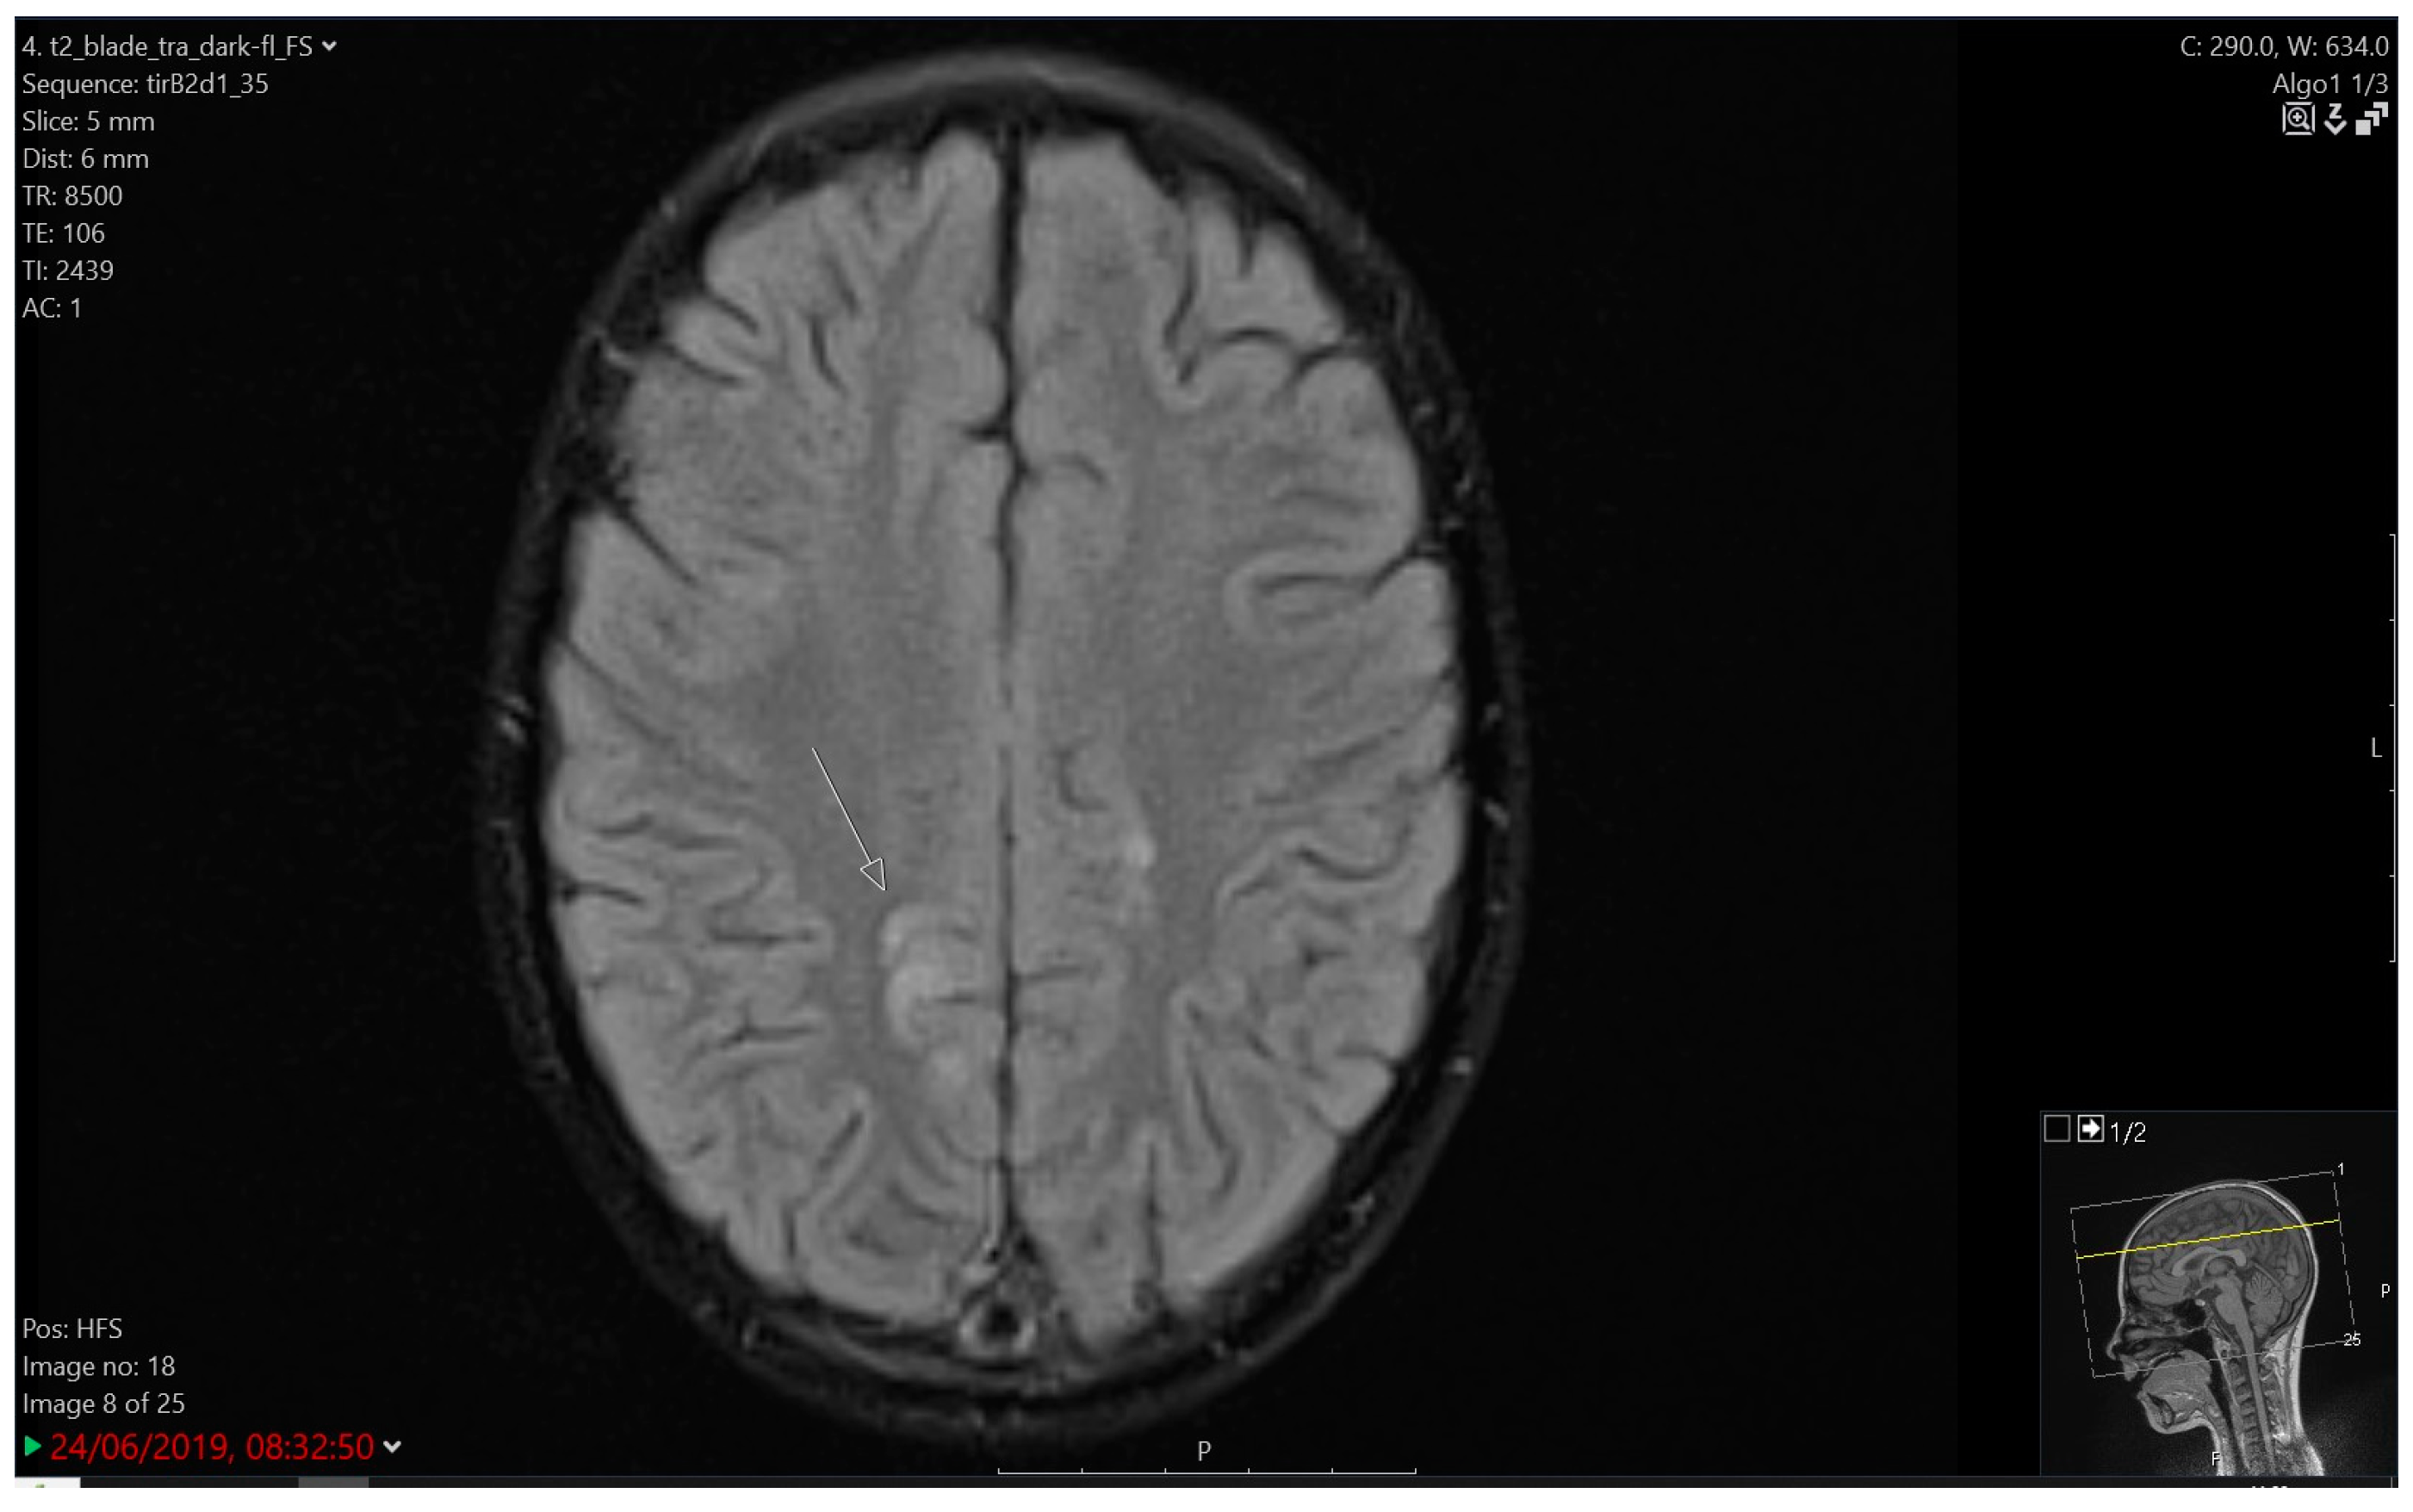

3.4.2. Imaging

| 3 | 7.5 | M | B | HR | Protocol II | Tonic-clonic seizure | 5 days | Very slow background activity | PRES | 3 | 1 year of AET, atrophic MRI brain changes |

| 4 | 7.5 | F | T | HR | Protocol IA | Atonic seizure, Subsequent right-sided hemiparesis | 2 days | Slower activity, high voltage slow waves left | Cerebro- vascular ischemia | 3 | Ongoing AET, atrophic MRI brain changes |

| 5 | 3.5 | F | B | HR | Protocol IA | Tonic status epilepticus | 10 min | Slower activity bilaterally | PRES | 4 | CR, atrophic MRI brain changes |

| 7 | 7.5 | F | B | IR | Protocol II | Tonic-clonic seizure | 30 s | Focal changes over FCT bilaterally with generalisation | LE | 3 | 5 years of AET; CTX modification |

| 8A | 6 | F | B | IR | Protocol II | Tonic seizure | 1 min | Slower activity CTP right | LE | 3 | Selective mutism |

| 8B | 10 | relapse | N/A | Protocol II-IDA | Complex partial seizure with generalisation; status epilepticus | 30 min | Focal changes left FCTO | LE, cortical oedema | 4 | 2 years of AET; ITT modification | |

| 9 | 3 | M | B | HR | Maintenance | Complex partial seizure with generalisation; status epilepticus | 2 h | Focal changes left | LE, pontine cavernoma, mineralising angiopathy | 4 | Two neurosurgical procedures; 5 years of AET |

| 11 | 4.5 | M | B | SR | Protocol II | Headache, vomiting | unknown | Not performed | LE, Chiari malformation type I | 2 | CR |